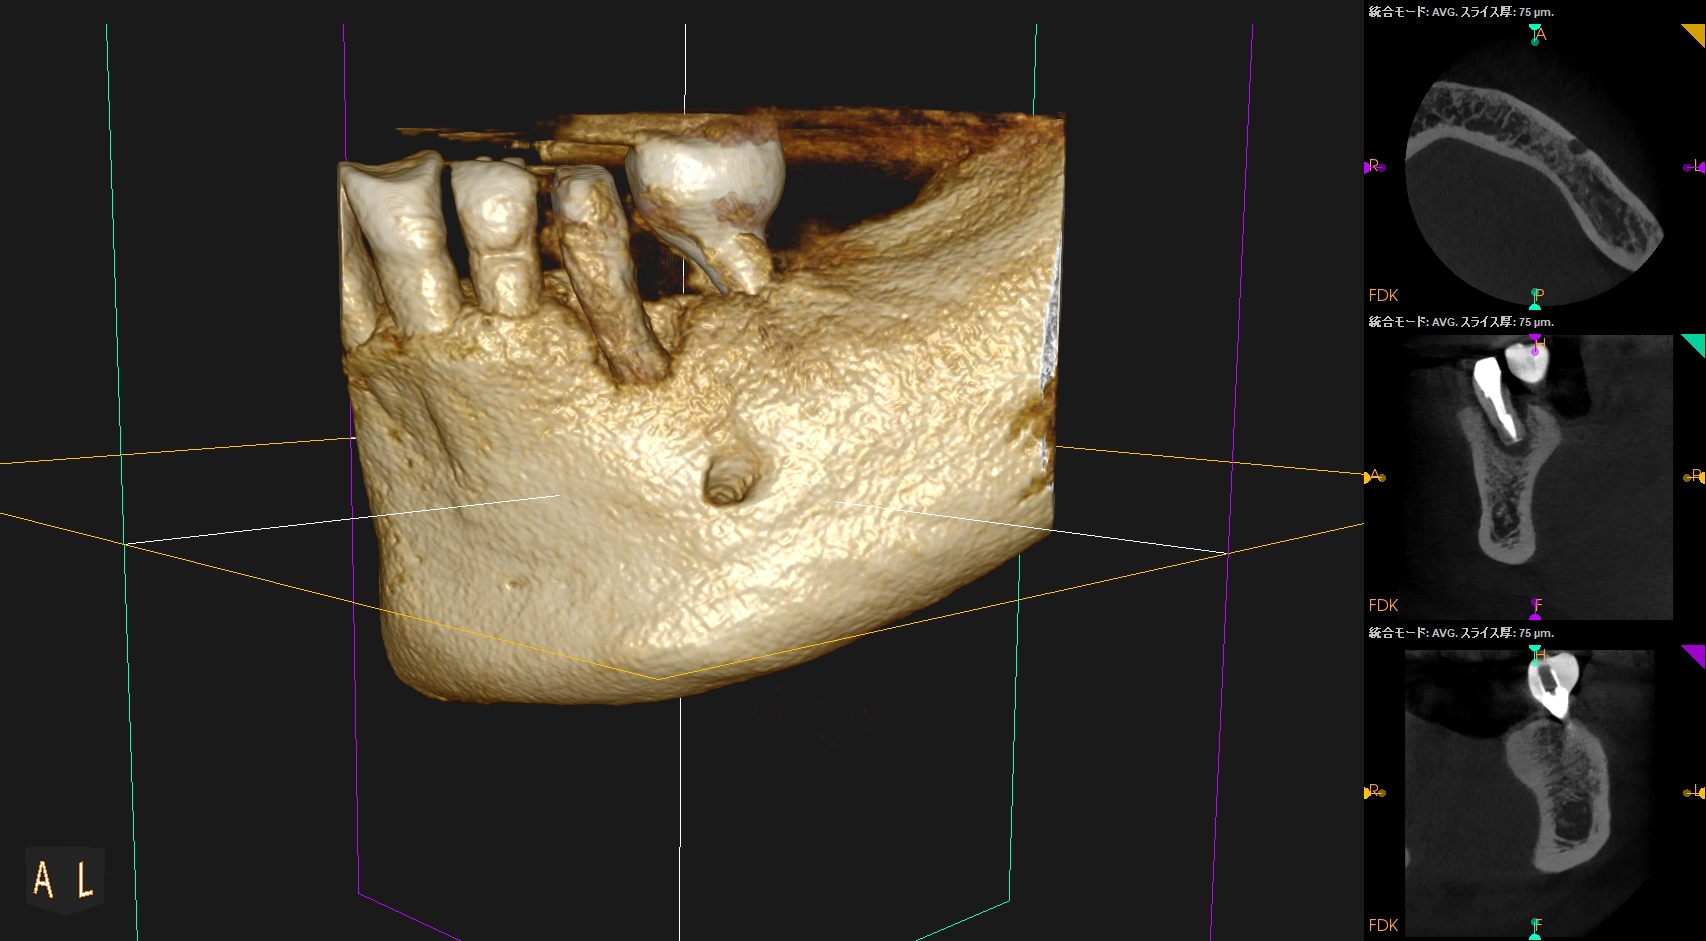

#20の周囲には歯槽骨がほぼないので容易に抜歯ができた。

術後にPA, CBCTを撮影した。

長いスクリューピンの除去には約50分かかったがIntentional Replantationは15分で終了した。